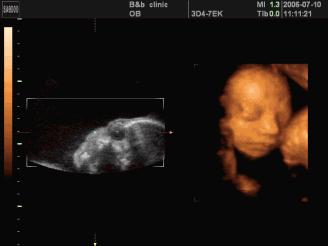

(孕16周的胎儿)

B超可以确认胎囊的位置、胎儿心脏跳动、胎儿大小、外表是否畸形,以及计算预产期,监控发育是否正常。虽然可以检查宝宝外表异常,但并不能查出唐氏综合症等染色体异常的情况。